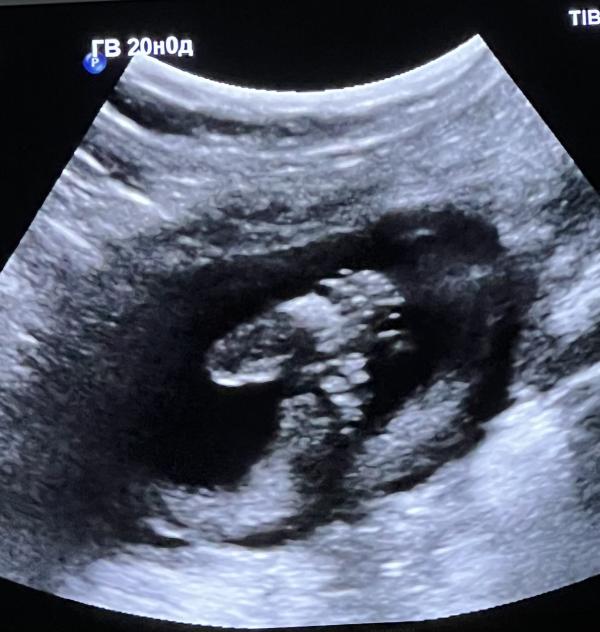

Несколько недель назад мне поставили : Центральное предлежание плаценты. До сегодняшнего дня я только и делала что представляла как мне делают КС. Просыпалась в ужасе.

1. Предлежания нет и не было.

В итоге все перемерили. С малышкой все хорошо.